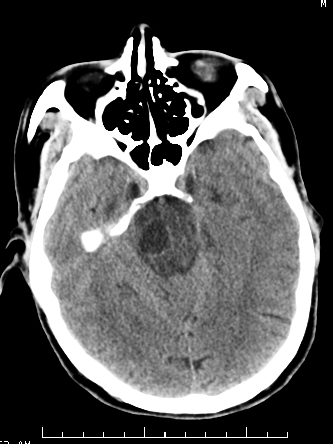

m/50,头昏头痛1月,近3天感觉左半肢体活动不利,自述半年前呈患肺tb,腰穿脑脊液未见特殊改变。现做头颅ct请大家会诊。

首先考虑肿瘤性病变,星形细胞瘤可能性大,不排外转移瘤。建议mri。

脑干占位,考虑转移瘤可能性大,不除外胶质瘤.

考虑为:脑干脓肿;不排除胶质瘤或转移瘤。

右侧基底节区缺血性脑梗塞.脑干区考虑结核.

可考虑结核,患者水肿范围大,囊性病灶边缘密度较高,不考虑胶质母细胞瘤